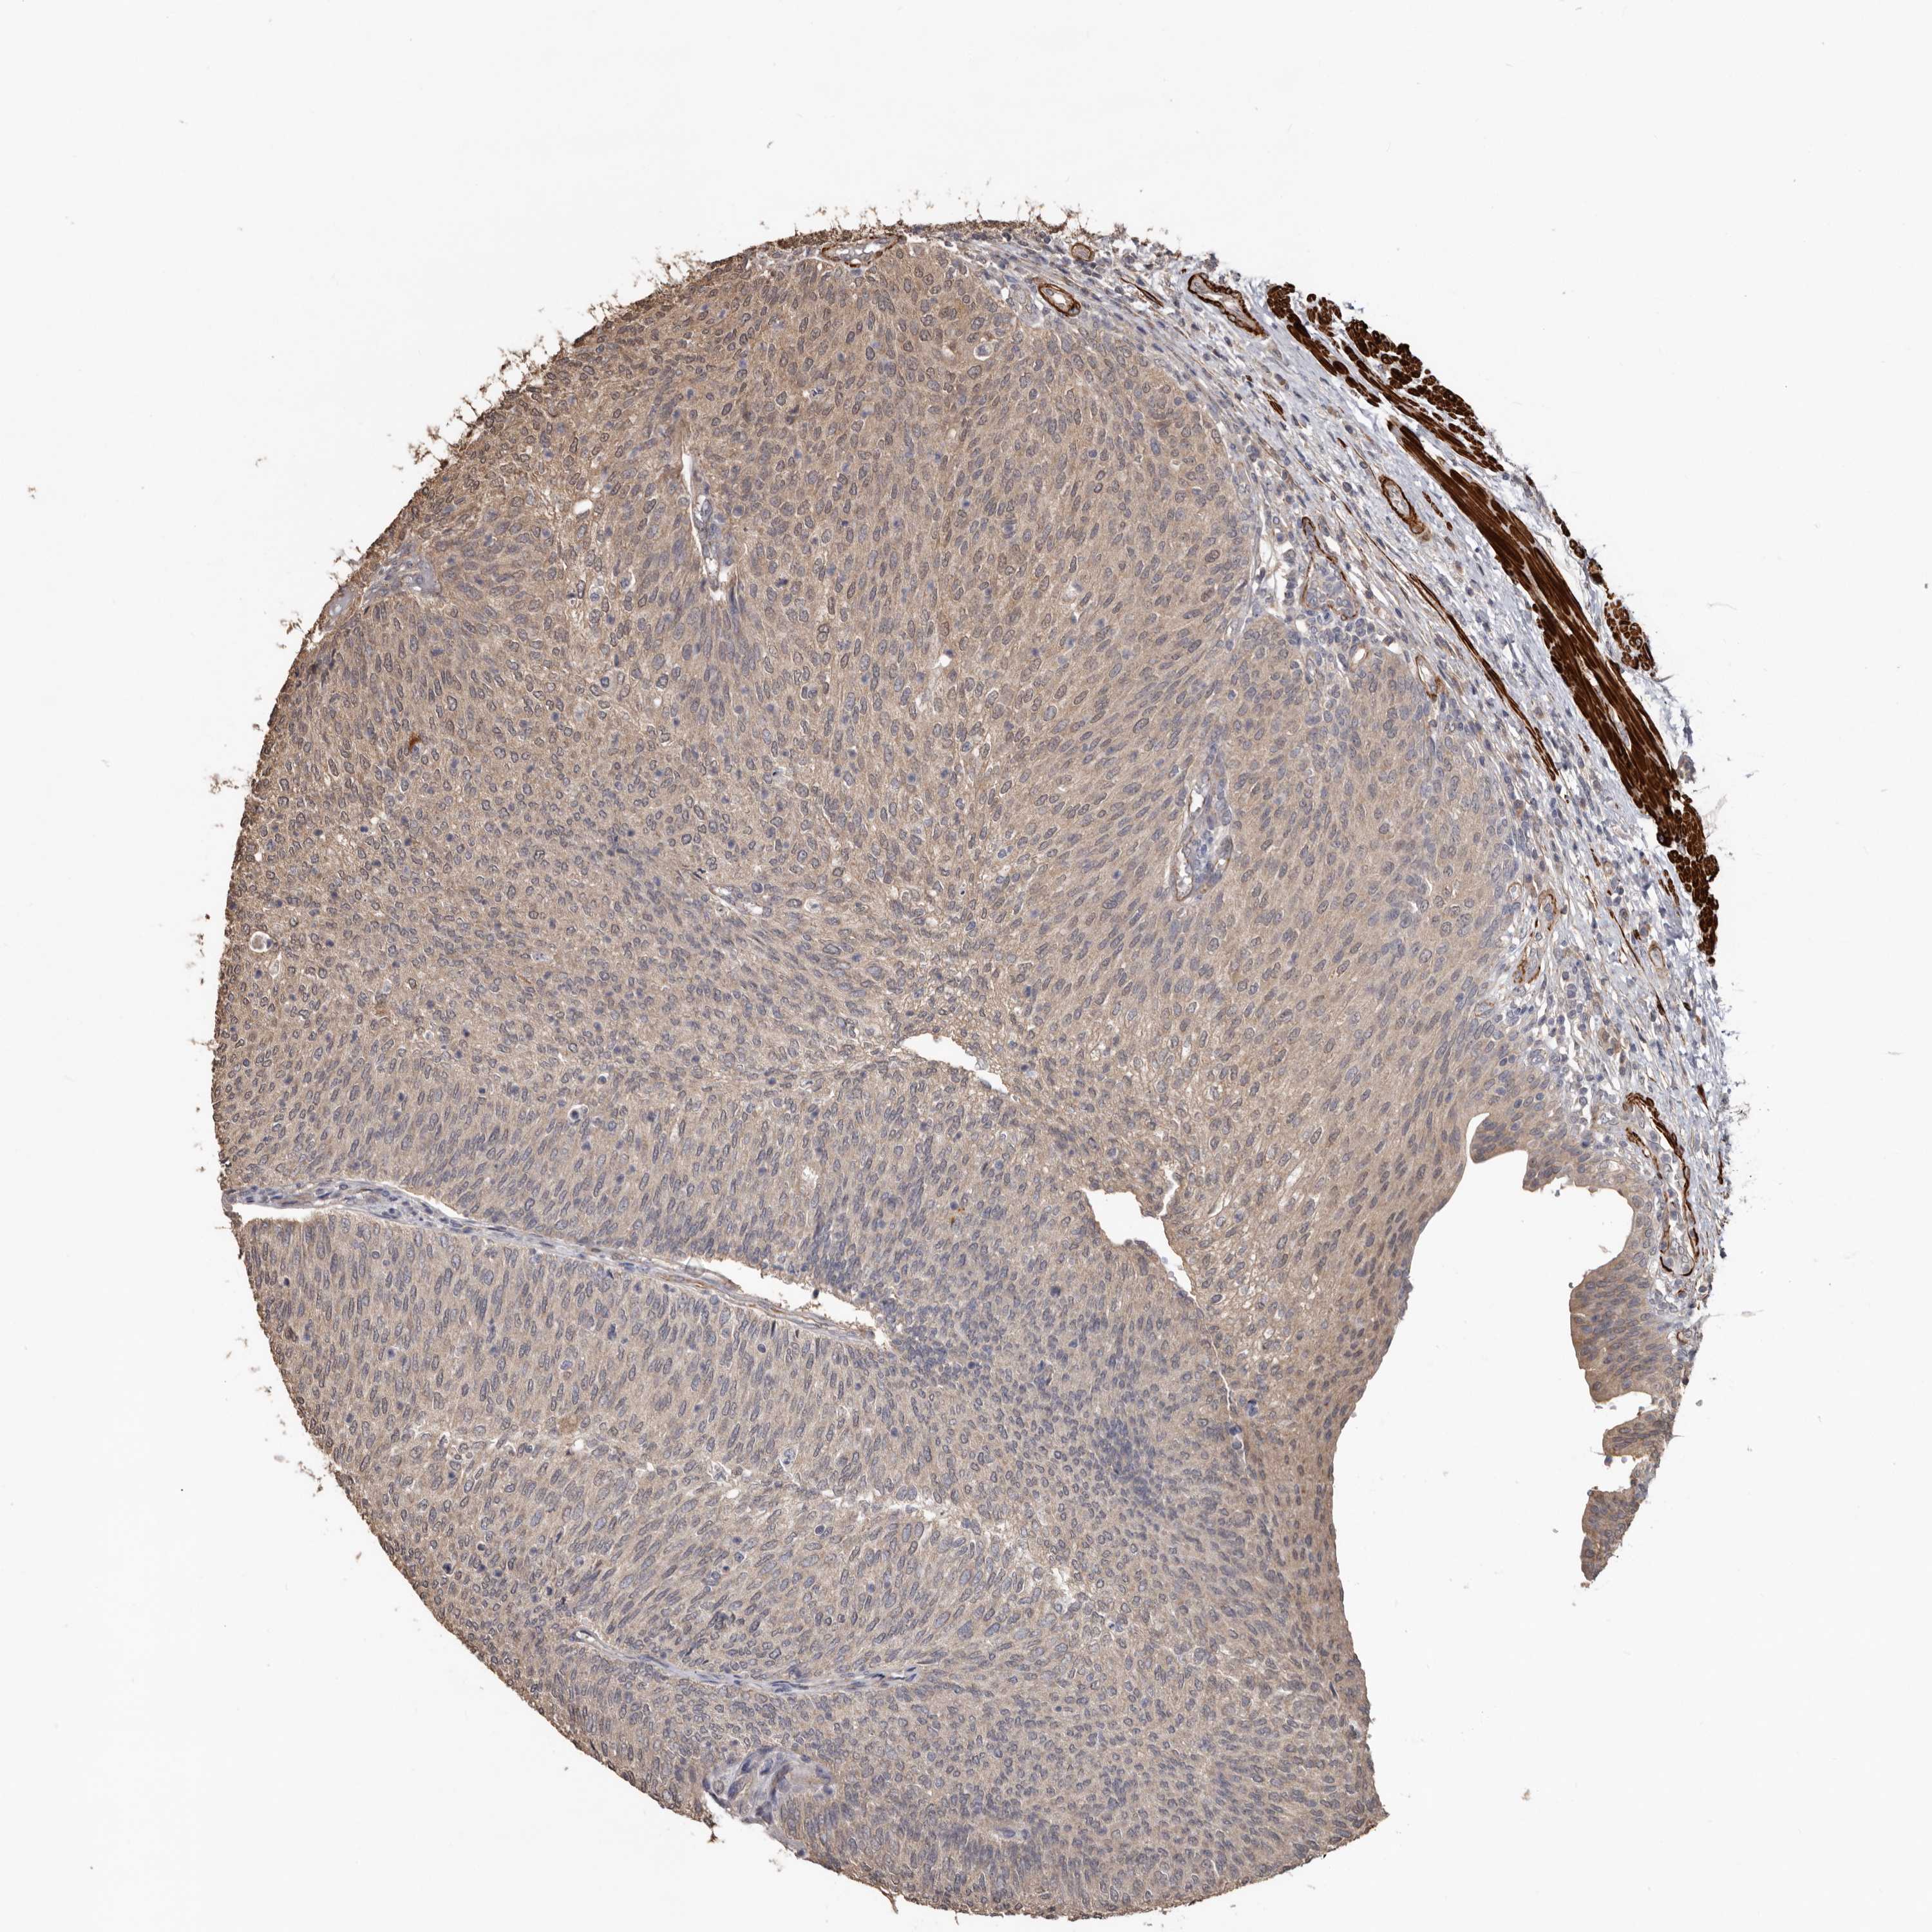

UROTHELIAL CANCER - Protein expressioni

A mouse-over function shows sample information and annotation data. Click on an image to view it in a full screen mode. Samples can be filtered based on level of antibody staining by selecting one or several of the following categories: high, medium, low and not detected. The assay and annotation is described here.

Note that samples used for immunohistochemistry by the Human Protein Atlas do not correspond to samples in the TCGA dataset.

Antibody stainingi

Antibody staining in the annotated cell types in the current human tissue is reported as not detected, low, medium, or high, based on conventional immunohistochemistry profiling in selected tissues. This score is based on the combination of the staining intensity and fraction of stained cells.

Each image is clickable and will lead to virtual microscopy that enables deeper exploration of all samples and also displays staining intensity scores, fraction scores and subcellular localization as well as patient and tissue information for each sample.

Antibody HPA027481

Antibody HPA028722

Urothelial carcinoma, Low grade

Urothelial carcinoma, High grade